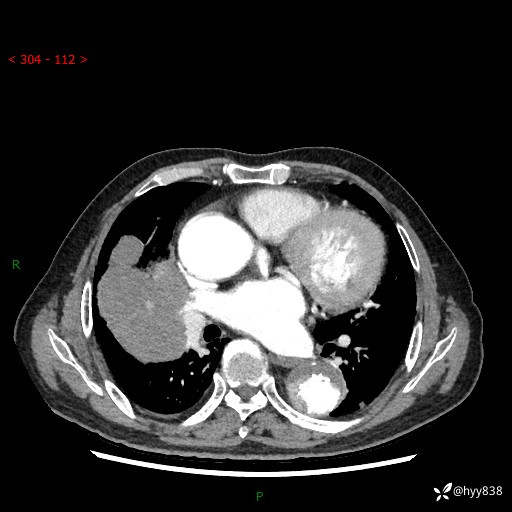

增强动脉期